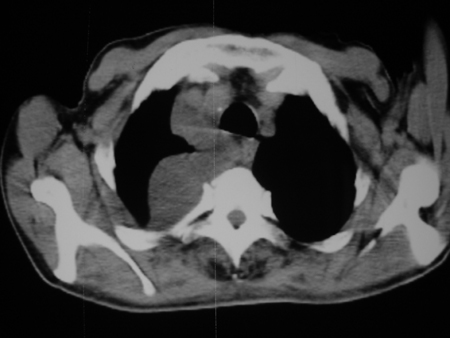

男77岁,胸痛就诊

右侧胸腔积液,部分包裹,右下肺膨胀不全,右下肺感染。

考虑右肺门占位并下叶不张 右胸包裹积液

右肺中叶及下叶炎症并胸腔积液(部分包裹),建议抽液后复查ct除外占位。

右侧胸腔积液,部分包裹,右下肺膨胀不全,右下肺感染